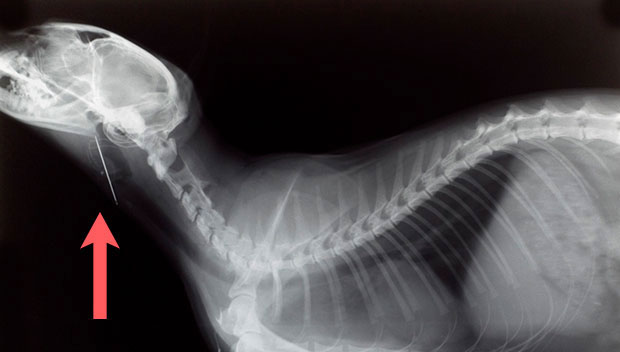

Katze mit Nadel in der Speiseröhre